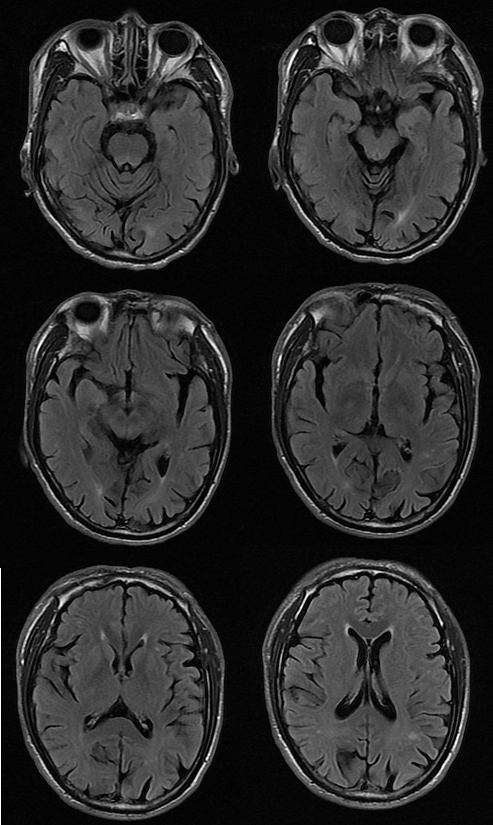

T2FLAIR

MRI 影像描述:T1W1 可见双侧苍白球对称高信号,T2、T2FLAIR、DWI 相应部位均未见确切异常信号。

普遍接受的 HE 颅脑 MR 常规成像特点为 T1WI 上基底节区尤其是苍白球双侧对称性高信号,其他部位如黑质、中脑被盖以及垂体等也可出现异常高信号;T2WI 上多无明显改变,组织学证实苍白球密度增高是猛沉积的结果。健康人在摄入锰之后可迅速被肝脏清除,并排出人胆道系统。肝硬化病人锰经胆道排泄减慢,导致血锰水平升高及脑中锰聚集增加。因锰离子在第 3 轨道有 5 个不配对电子而具有较大磁矩,能明显缩短 T1 弛豫时间,导致 T1WI 高信号。